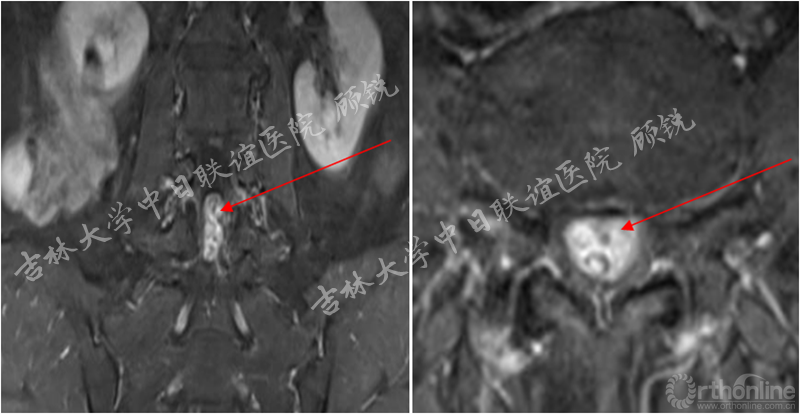

MRI平扫如下:

(L4-5)

滑脱椎体后方椎管内见异常信号,是游离髓核(硬膜内)?椎管内肿瘤(神经源性、转移)?血管畸形?还是其他其他?组内会诊认为以疾病一元论解释患者的症状、体征考虑因滑脱椎导致马尾神经冗余的可能性大。进一步检查了增强腰椎MRI。

增强MRI增强如下:

腰椎增强MRI示:

占位组织强化明显为实质病变,依据瘤体与硬膜间呈锐角;T1W1:等信号;T2W1:混杂高信号STIR:环状增强,Non-enhancement area(+)。经科内会诊该患者的诊断为:峡部裂型腰椎滑脱(L5 Ⅱ度)、腰椎管内占位性病变(神经鞘瘤?)。Ozawa H, Aizawa T, Kanno H.Epidemiology of surgically treated primary spinal cord tumors in Miyagi, Japan.Neuroepidemiology. 2013;41(3-4):156-60